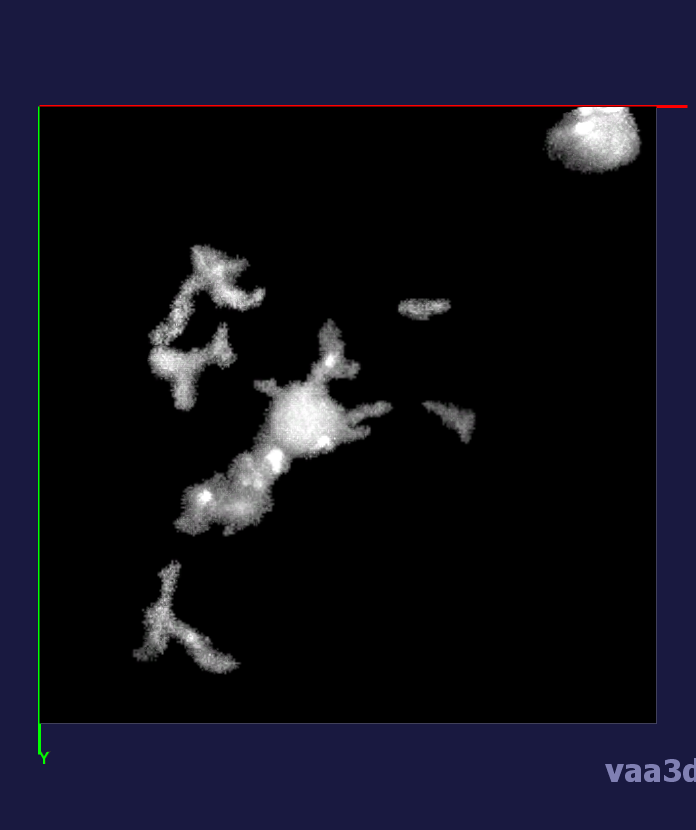

The 3D movies of microglia were imaged over 20 minutes with z-stacks taken at one minute intervals, containing single or multiple microglia per field of view. Some of the images were cropped from a larger field of view containing about 10 different cells and two images were imaged from a zoomed in view of one individual cell. The images ranged from a horizontal pixel width of .01 um and a vertical pixel width of .01 um to horizontal pixel width of .2 um and a vertical pixel width of .2 um. In the 3D images, there is variation in intensity contrast throughout the cell, non-structural noise, and fluorescence bleeding through z-stack due to the lengthy imaging technique which makes it difficult to visualize and process. The images were pre-processed using histogram equalization which increased the intensity throughout the cell but further increased noise in the background.

In our experiments, we compare the coupled TuFF-BFF microglia segmentation results with those given by L2S [21] and the Chan-Vese segmentation method [22]. The groundtruth in 3D was attained by manually tracing the object slice by slice from the z-stack. It must be noted that this was done by eye and could have some error. Figure 2 shows the visual comparison of the segmentation results for our dataset. Our result shown on the third column captures both the soma and processes. Figure 3 shows the Dice coefficient comparison of each segmentation method to the ground truth. Since the soma is much larger than the fine processes in the microglia, the processes have less volumetric impact on the similarity score. As explained in Section 1, segmenting the processes is important for quantifying the extension from the soma and its volume of surveillance. We use the Dice coefficient to quantitatively compare the ramification by taking the convex hull of the resulting segmentation. The Dice coefficient is a similarity measure that is computed using with where is the ground truth and is the compared image.